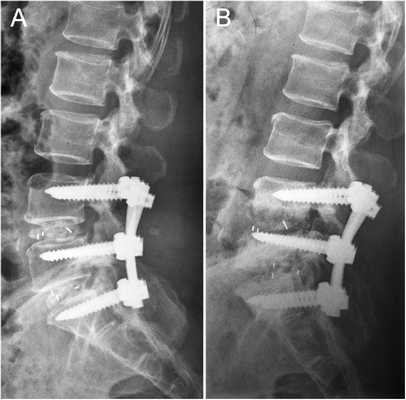

Чтобы иммобилизация позвоночно-двигательного сегмента была максимально надежной, нередко операция дополняется выполнением транспедикулярной фиксации. В таком случае устанавливаются специальные металлические конструкции, которые еще более упрочняют скрепление тел позвонков.

Метод PLIF подразумевает удаление отростков с двух сторон от позвонка. После этого осуществляется радикальная дискэктомия. По обеим сторонам позвонка устанавливаются кейджи.

Иногда их заменяют расширяющимися имплантатами. Поскольку они обладают меньшими размерами, нейрохирургу достаточно провести медиальную двустороннюю фасетэктомию (удаление фасеточных суставов) и удалить только студенистое ядро диска. Такие имплантаты оснащены винтами. Их раскручивают специальным ключом, благодаря чему кейджи прочно фиксируются в заданном положении.